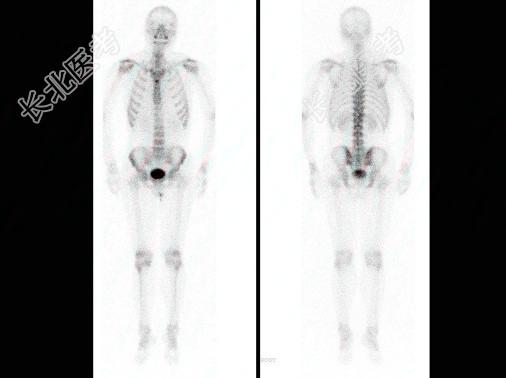

多项选择题男,肝癌术后1年, 诉腰背痛5个月,行全身骨显像如图, 碱性磷酸酶明显增高,可能的诊断是 ( )

A、胸12“冷区”

B、胸12有溶骨性病变

C、胸12骨转移瘤

D、大致正常的骨影像

E、肝癌骨转移“冷区”较常见